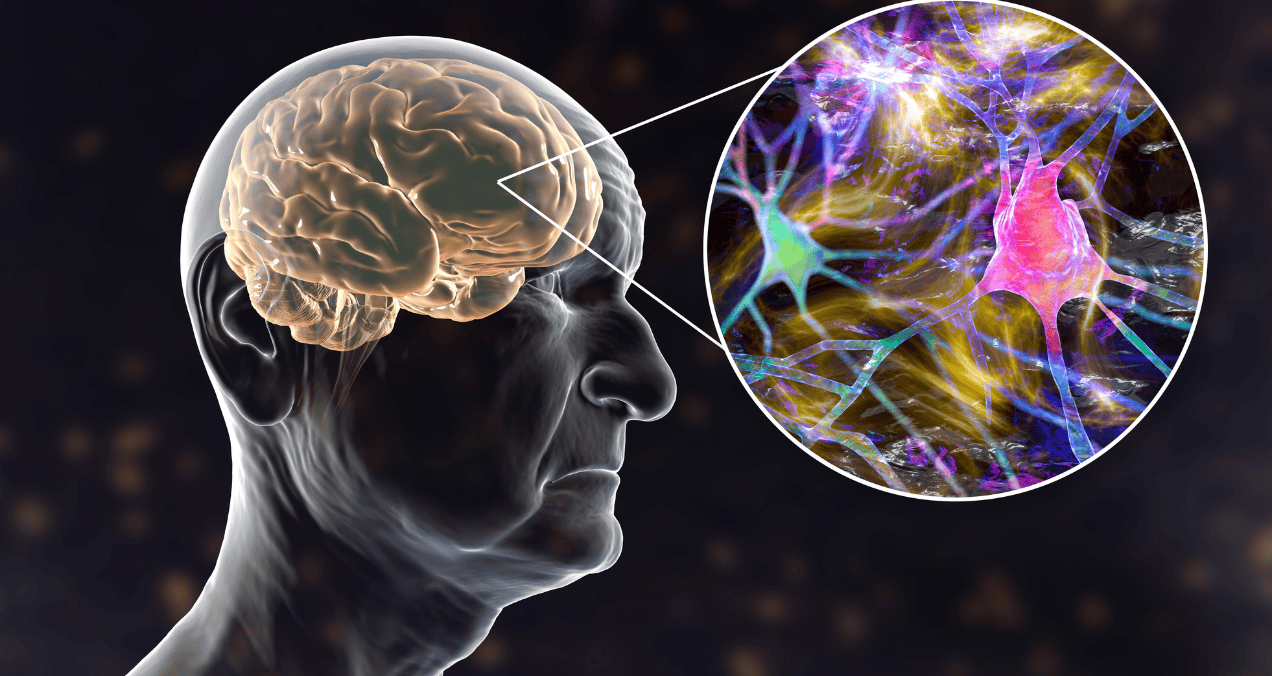

Neuralink, la empresa fundada por Elon Musk, tiene previsto iniciar la producción masiva de su implante de...

Científicos de la Universidad Nacional de Singapur identificaron un metabolito presente en el organismo como posible herramienta...

Un grupo de investigación dirigido por la Facultad de Medicina Yong Loo Lin de la Universidad Nacional...